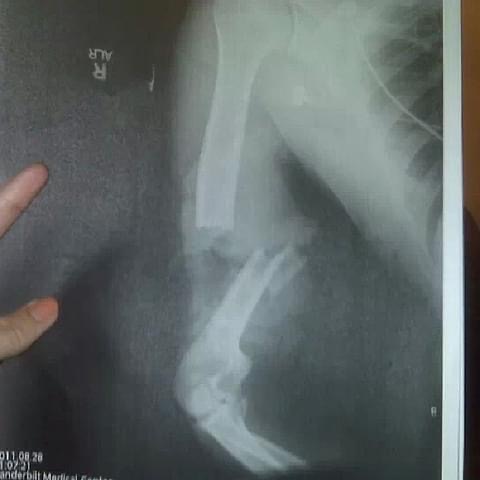

In 2011, Smith was involved in a catastrophic motorcycle accident in Nashville, Tennessee, when he was struck by a distracted driver. The collision resulted in the loss of his right arm above the elbow and put his life and military career at risk. Doctors told him he might never compete again.

Following the accident, Smith endured extensive surgeries and medical setbacks, including kidney failure, and spent two years in intense rehabilitation.